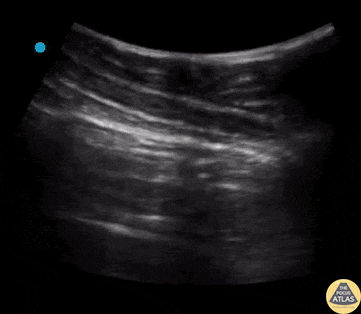

Pulmonary - Lung Point Finding

Lung point is a pathognomonic finding on US for pneumothorax. It refers to the junction between healthy lung and collapsed lung. This is represented in the US recording as lung sliding seen on the left of the pleural line but no lung sliding seen on the right of the pleural line. Contributors: Dimitri Livshits, DO; Jane Belyavskaya, MD; Chris Hanuscin, MD Kings County/SUNY Downstate